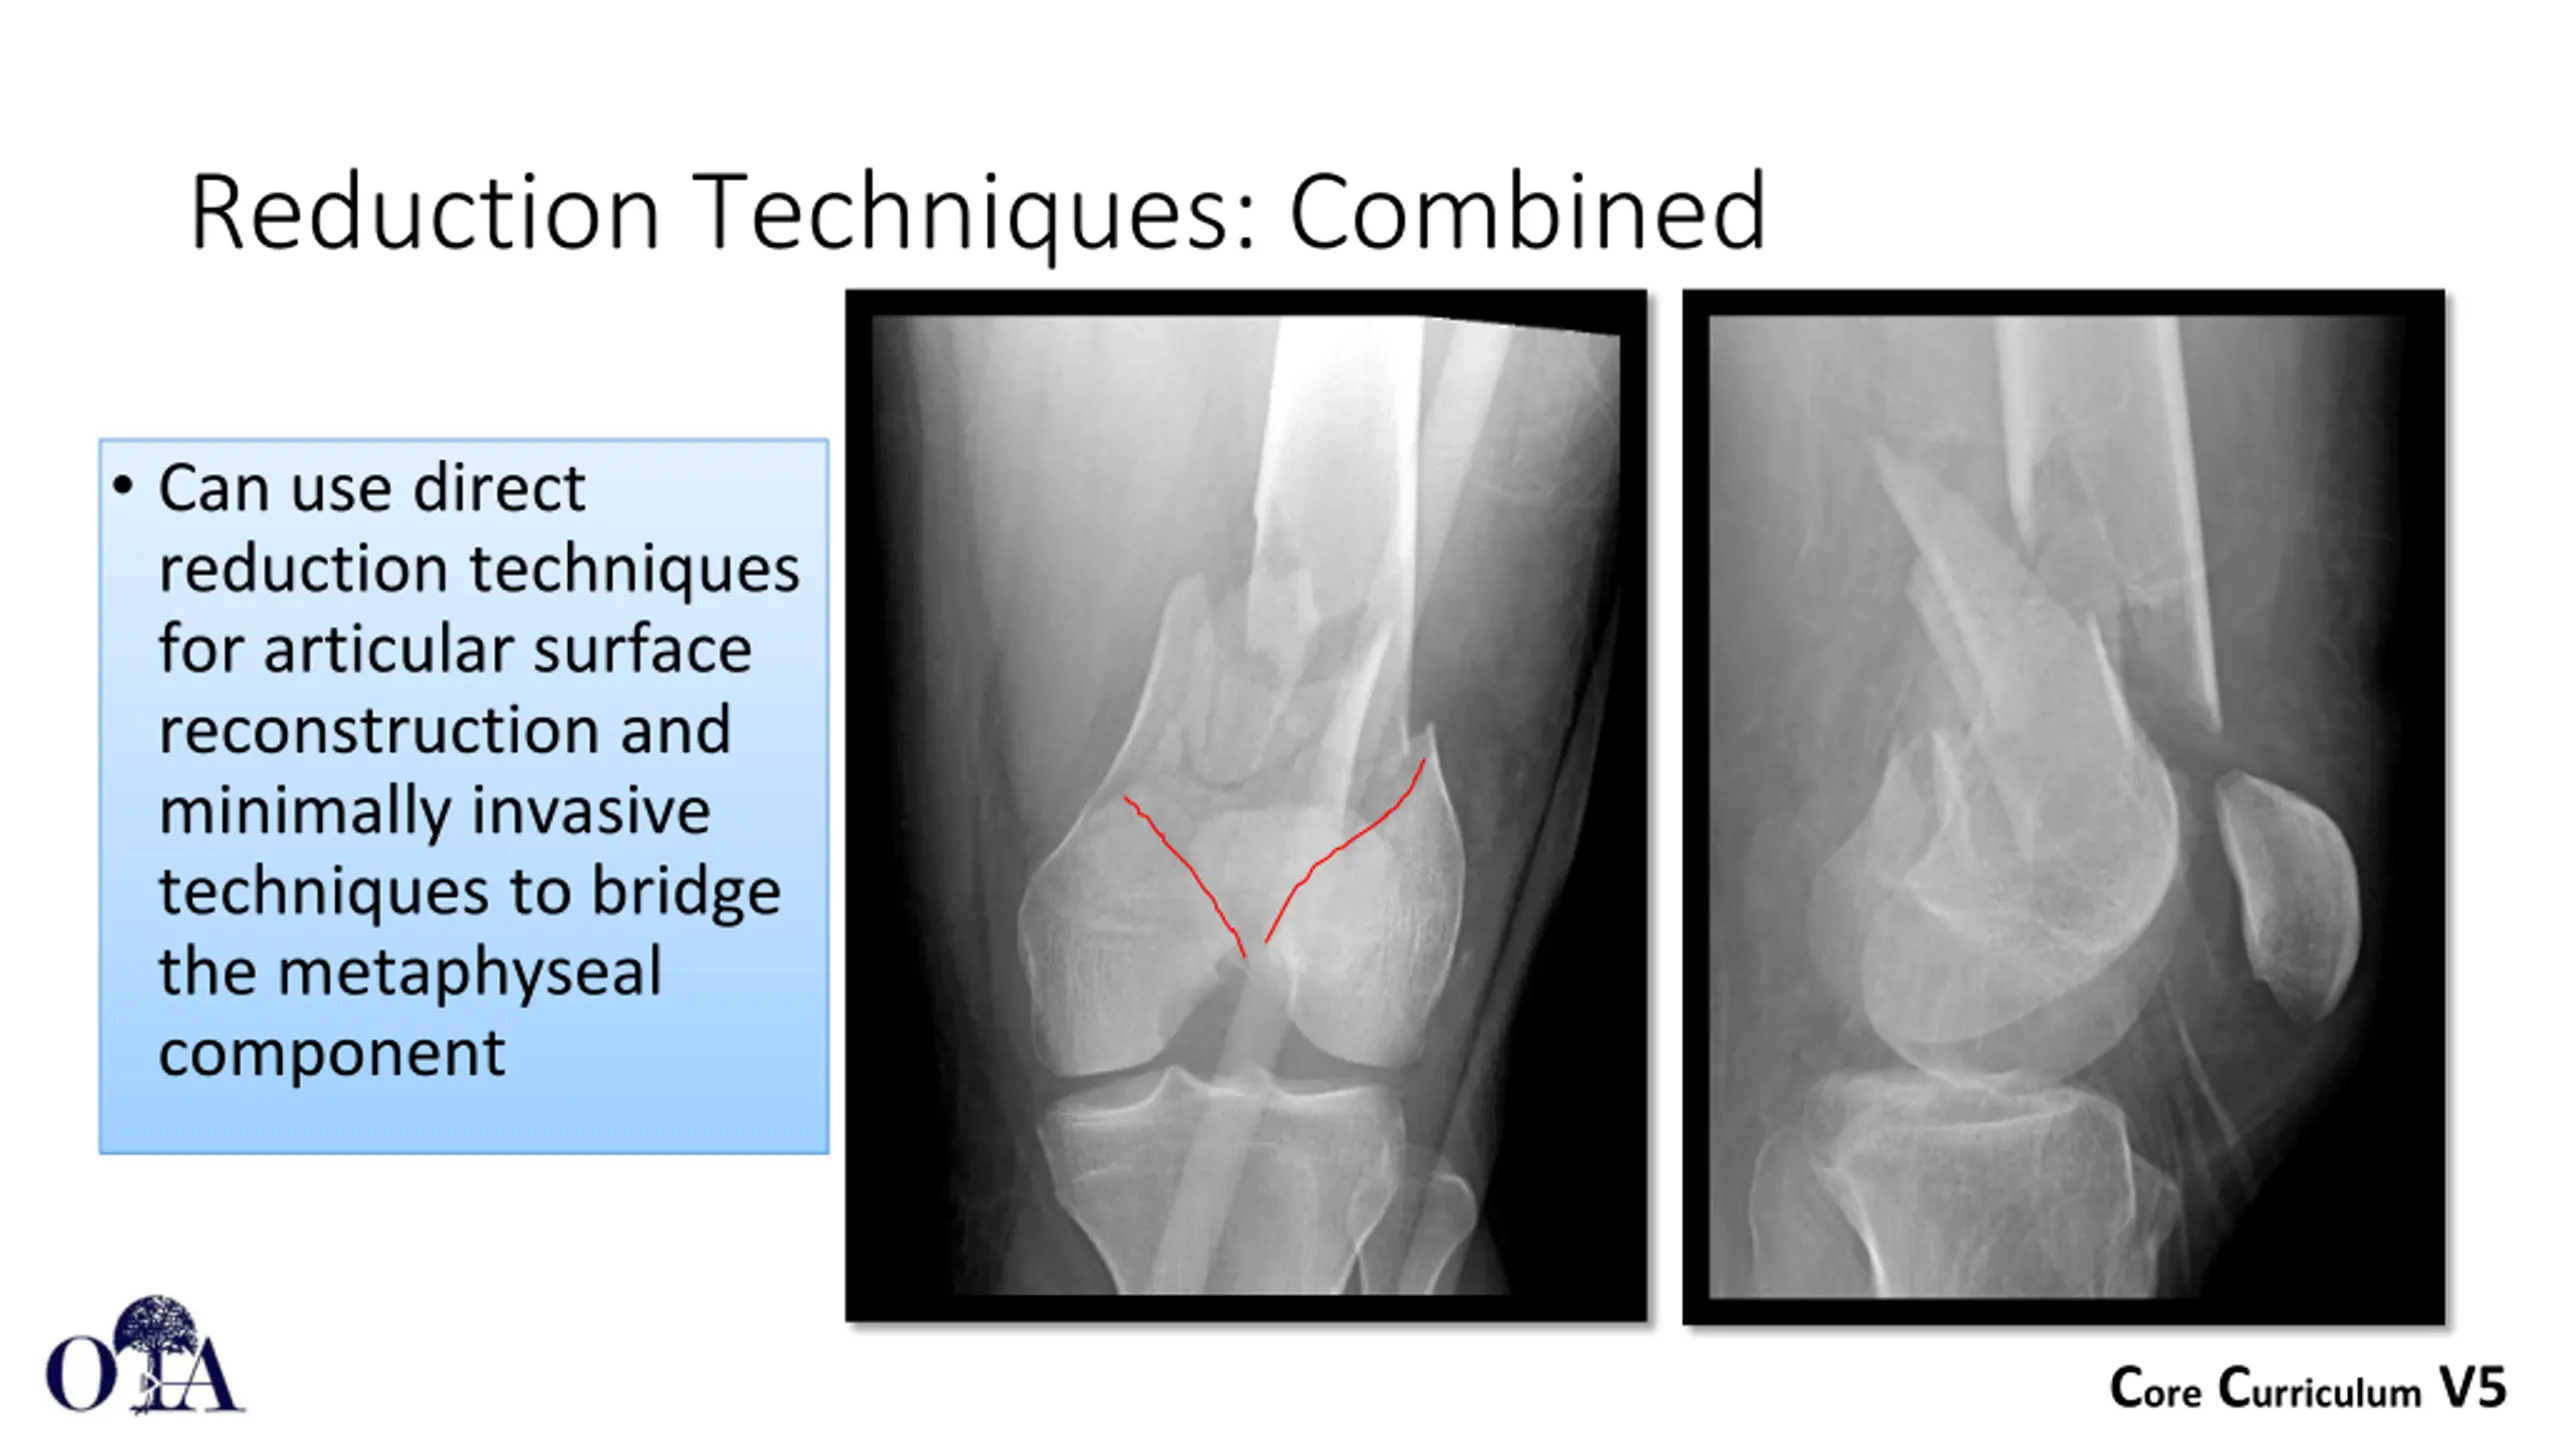

Reduction Techniques: Combined Can use direct reduction techniques for articular surface reconstruction and minimally invasive techniques to bridge the metaphyseal component Core Curriculum V5